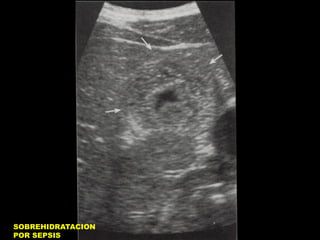

SOBREHIDRATACION

POR SEPSIS

Engrosamiento difuso de

Pared Vesicular

PARED VESICULAR Y ASCITIS